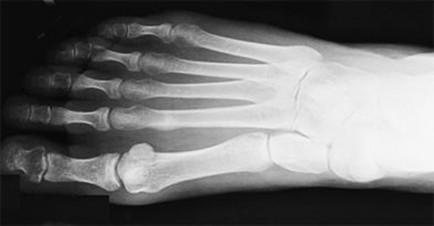

A 42-year-old man with diabetes presents for treatment of a swollen foot (Slide). He does not recall the onset of swelling, and he states that his foot is not painful. On examination, the foot is hot to touch and swollen. Upon radiographic examination, no deformities are evident. Which of the following treatment options should be used next: